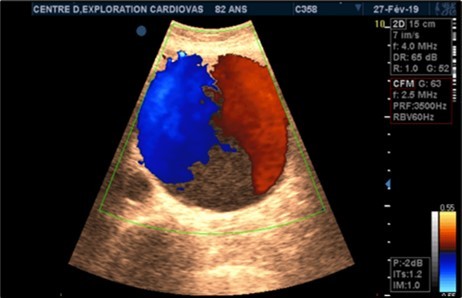

Aneurysms were thrombosed in 24 patients (75%). (Figure 3) and (Figure 4) Arterial occlusion was found in 11 patients (73.33%) and significant stenosis in 4 patients (36.36%). (Table 7).

Figure 3.Large fusiform subrenal abdominal aortic aneurysm of 9.28cm thrombosed at 4/5 in an 82-year-old woman (CEC ‘Saint-Esprit’ from AMP-MCV).

Figure 4.Large fusiform subrenal abdominal aortic aneurysm of 9.28cm thrombosed at 4/5 in an 82-year-old woman (CEC ‘Saint-Esprit’ from AMP-MCV).